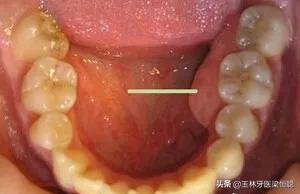

臨床上,我們常常遇到患者說“牙齦上鼓了個包,硬硬的”,或鑲牙的老人說“牙床壓著疼”,通??赡苁浅霈F(xiàn)了牙槽骨骨質(zhì)增生。

口腔內(nèi)牙槽骨的骨質(zhì)增生是指牙齦區(qū)域的牙槽骨出現(xiàn)骨質(zhì)增生性突起,在臨床上比較常見。

骨質(zhì)增生的形式多種多樣,因所在部位不同而有其各自的特點,在口腔中多表現(xiàn)多圓錐狀突起或小骨刺,一般沒有的臨床癥狀,有時候伴有輕微的疼痛,可以通過X光攝片清晰地辨認骨質(zhì)增生的部位和增生的程度。